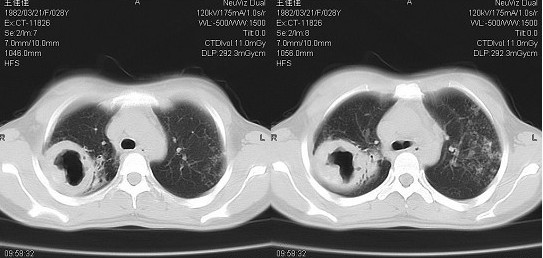

- 肺部同时可有渗出、干酪、纤维、空洞、胸膜增厚、钙化等不同病期的病变。空洞多在一侧或两侧上中肺野,可单发或多单发,空洞的壁被较厚的纤维组织所包围,空洞周围的肺组织多伴有进行性支气管播散病灶和纤维修补同时存在,并常以纤维增生为主。

- 患侧肋间隙变窄,纵膈、气管阴影向患侧移位。

- 患侧肺门上提,肺纹理呈垂柳状,膈肌上升。

- 对侧肺呈代偿性肺气肿,心影变小呈滴状心,膈肌下降。

- 有支气管播散病灶、胸膜增厚粘连,膈肌可呈幕状。

- CT可见到明显的支气管扩张、肺纤维化、肺气肿、肺不张等表现。